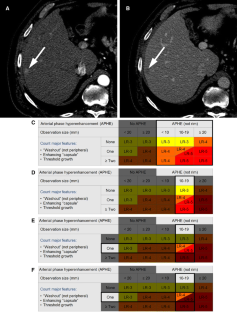

LI-RADS® algorithm: CT and MRI

The Liver Imaging Reporting and Data System (LI-RADS®) is an imaging-based diagnostic system applicable in patients at high risk of hepatocellular carcinoma (HCC). In LI-RADS, each liver observation is assigned a category that reflects probability of benignity, HCC, or other malignancy. Familiarity with the LI-RADS diagnostic algorithm is necessary to appropriately implement LI-RADS in clinical practice. This review discusses steps necessary for application of the LI-RADS algorithm and provides examples illustrating each step.